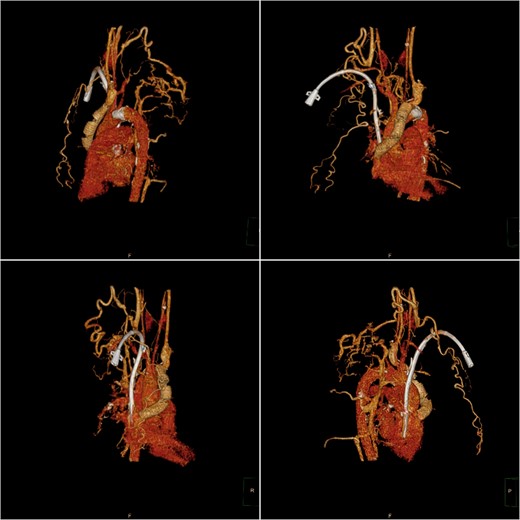

Postoperative computed tomography (CT) three-dimensional reconstruction shows the artificial blood vessel and tunneled cuffed catheter deformation.

After a cardiac surgery consultation, the innominate-to-right-atrial bypass grafting technique under extracorporeal circulation and right atrial thrombus removal was planned. After anesthesia induction, the patient underwent central venous catheter placement in the left femoral vein as a route for anesthetic and vasoactive drugs. After the patient was fully heparinized, the sternum was opened for aortic cannulation and inferior vena cava drainage to establish extracorporeal circulation. During the operation, the right atrium was opened and a large calcified thrombus attached to the tunneled cuffed catheter was removed. Subsequently, the narrowed part of the unnamed vein was excised, and an artificial blood vessel (Gore R14030030L14mm*30 cm*30 cm) was anastomosed to the proximal end. After excising part of the right atrial appendage, the distal end of the artificial blood vessel was anastomosed to it, forming an innominate vein-to-right atrium artificial blood circulation (Fig. 1). The tracheal catheter was successfully removed after the operation. The patient currently has no symptoms such as arm swelling. The artificial blood vessel is unobstructed (Fig. 2), and normal dialysis is performed using the tunneled cuffed catheter.